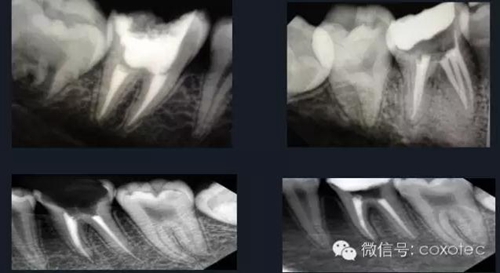

熱牙膠根管充填技術(shù)是利用牙膠加熱軟化后具有流動(dòng)性的特點(diǎn),使根管充填的效果更理想。

熱牙膠加壓充填技術(shù)是在加熱軟化牙膠尖的同時(shí),通過(guò)側(cè)向或(和)垂直向的壓力,將牙膠壓緊以嚴(yán)密封閉根管系統(tǒng)。以替代傳統(tǒng)冷的側(cè)方加壓充填的一種儀器。

由于它可以快速精確,密實(shí)的三維根管充填而受到醫(yī)生廣泛推崇,必將為根管充填帶來(lái)革命性的影響。

①選擇符合根管錐度的主牙膠尖,標(biāo)記工作長(zhǎng)度后切斷牙膠尖端

0.5~1mm,并有確實(shí)的回拉感。

②去除距離根尖孔3~5MM以上牙膠。

③選擇合適的攜熱器,確定攜熱器工作長(zhǎng)度為根管工作長(zhǎng)度減去3-5毫米。

④選擇合適的垂直加壓器,并確定加壓器工作長(zhǎng)度,多把加壓器長(zhǎng)度遞減配合使用。

⑤選擇合適的熱牙膠充填器頭,標(biāo)記好需要充填的長(zhǎng)度。

⑥將根管內(nèi)注入樹(shù)脂類(lèi)根管封閉劑后,再將牙膠尖放入根內(nèi)。

⑦使用手用加壓器垂直擠壓致密,垂直加壓器應(yīng)該從大號(hào)至小號(hào)。

⑧注射手法:輕,穩(wěn),慢